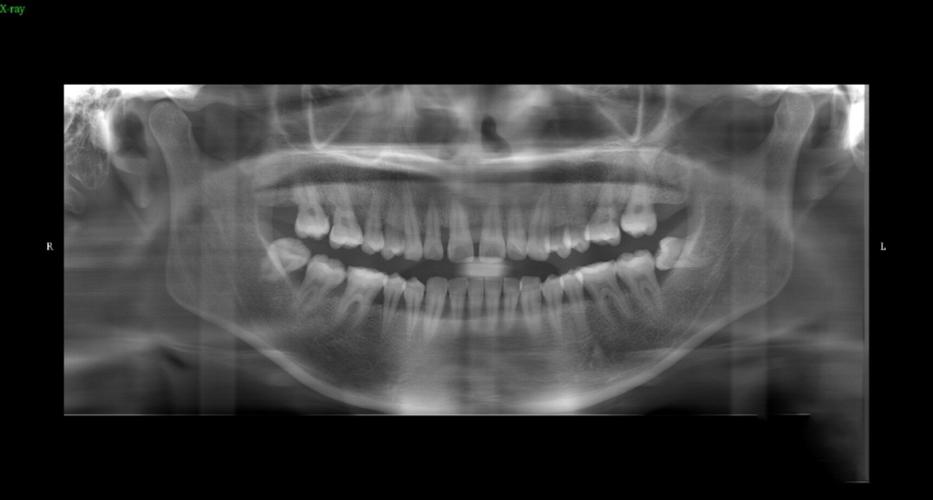

牙齿并非孤立存在,其下方有牙根(牙体组织的主要支撑结构),周围包裹着牙槽骨(固定牙齿的骨骼),拍片(如根尖片、全景片)能清晰显示牙根的形态、长度、是否有弯曲、吸收或断裂,以及牙根间是否存在骨间隔、囊肿或炎症,若患者牙根存在先天弯曲或过短,盲目施加矫正力可能导致牙根吸收甚至牙齿脱落;而埋伏牙(未正常萌出的牙齿)或多生牙(额外生长的牙齿),只有通过拍片才能准确定位其位置和方向,避免矫正中误伤。

牙齿的移动依赖于牙槽骨的改建(压力侧吸收、牵引侧增生),而颌骨的大小、形态直接影响矫正方案的设计,头颅侧位片能测量颌骨的长度、宽度、高度,判断是否存在“地包天”“龅牙”等骨性畸形——若骨性问题突出,可能需要配合正颌手术才能达到理想效果;全景片则可观察牙槽骨的高度和厚度,若牙槽骨因牙周病等原因吸收严重,牙齿移动时可能暴露牙根,甚至引发松动,拍片还能发现颌骨内的囊肿、肿瘤等病变,避免在矫正过程中刺激病灶。

牙周是牙齿的“土壤”,其健康状况直接决定矫正的可行性和安全性,牙周病患者常存在牙槽骨吸收、牙龈萎缩等问题,若未拍片评估就直接矫正,牙齿移动可能加速骨吸收,导致牙齿松动甚至脱落,通过拍片(如曲面断层片、CBCT),医生能判断牙周组织是否耐受矫正力,并制定分阶段治疗方案(先治疗牙周病,再开始矫正)。

| 全景片(曲面断层片) | 全口牙齿、牙根、牙槽骨、颌骨、上颌窦、下颌神经管等 | 观察牙齿数量、萌出方向、牙根形态,判断牙槽骨高度、有无囊肿/埋伏牙 |

| CBCT(锥形束CT) | 三维重建牙齿、牙根、牙槽骨、神经血管等精细结构 | 精准定位复杂病例(如埋伏牙、种植体植入),评估骨量,降低神经损伤风险 |